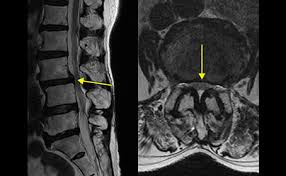

🩻 진단 방법

- MRI: 신경압박 정도, 협착 위치·범위 정확하게 파악